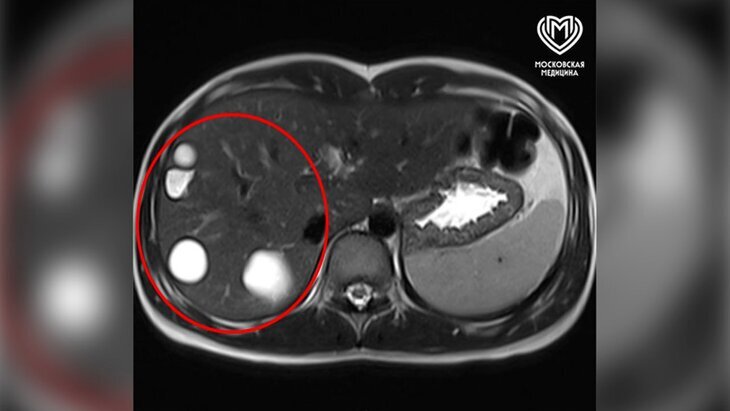

По итогам обследования врачи выявили в печени девочки пять эхинококковых кист крупных размеров. В ведомстве отметили, что заражение легочным червем (эхинококком) происходит при контакте с животными или их выделениями, а также при употреблении немытых овощей, фруктов и зелени.